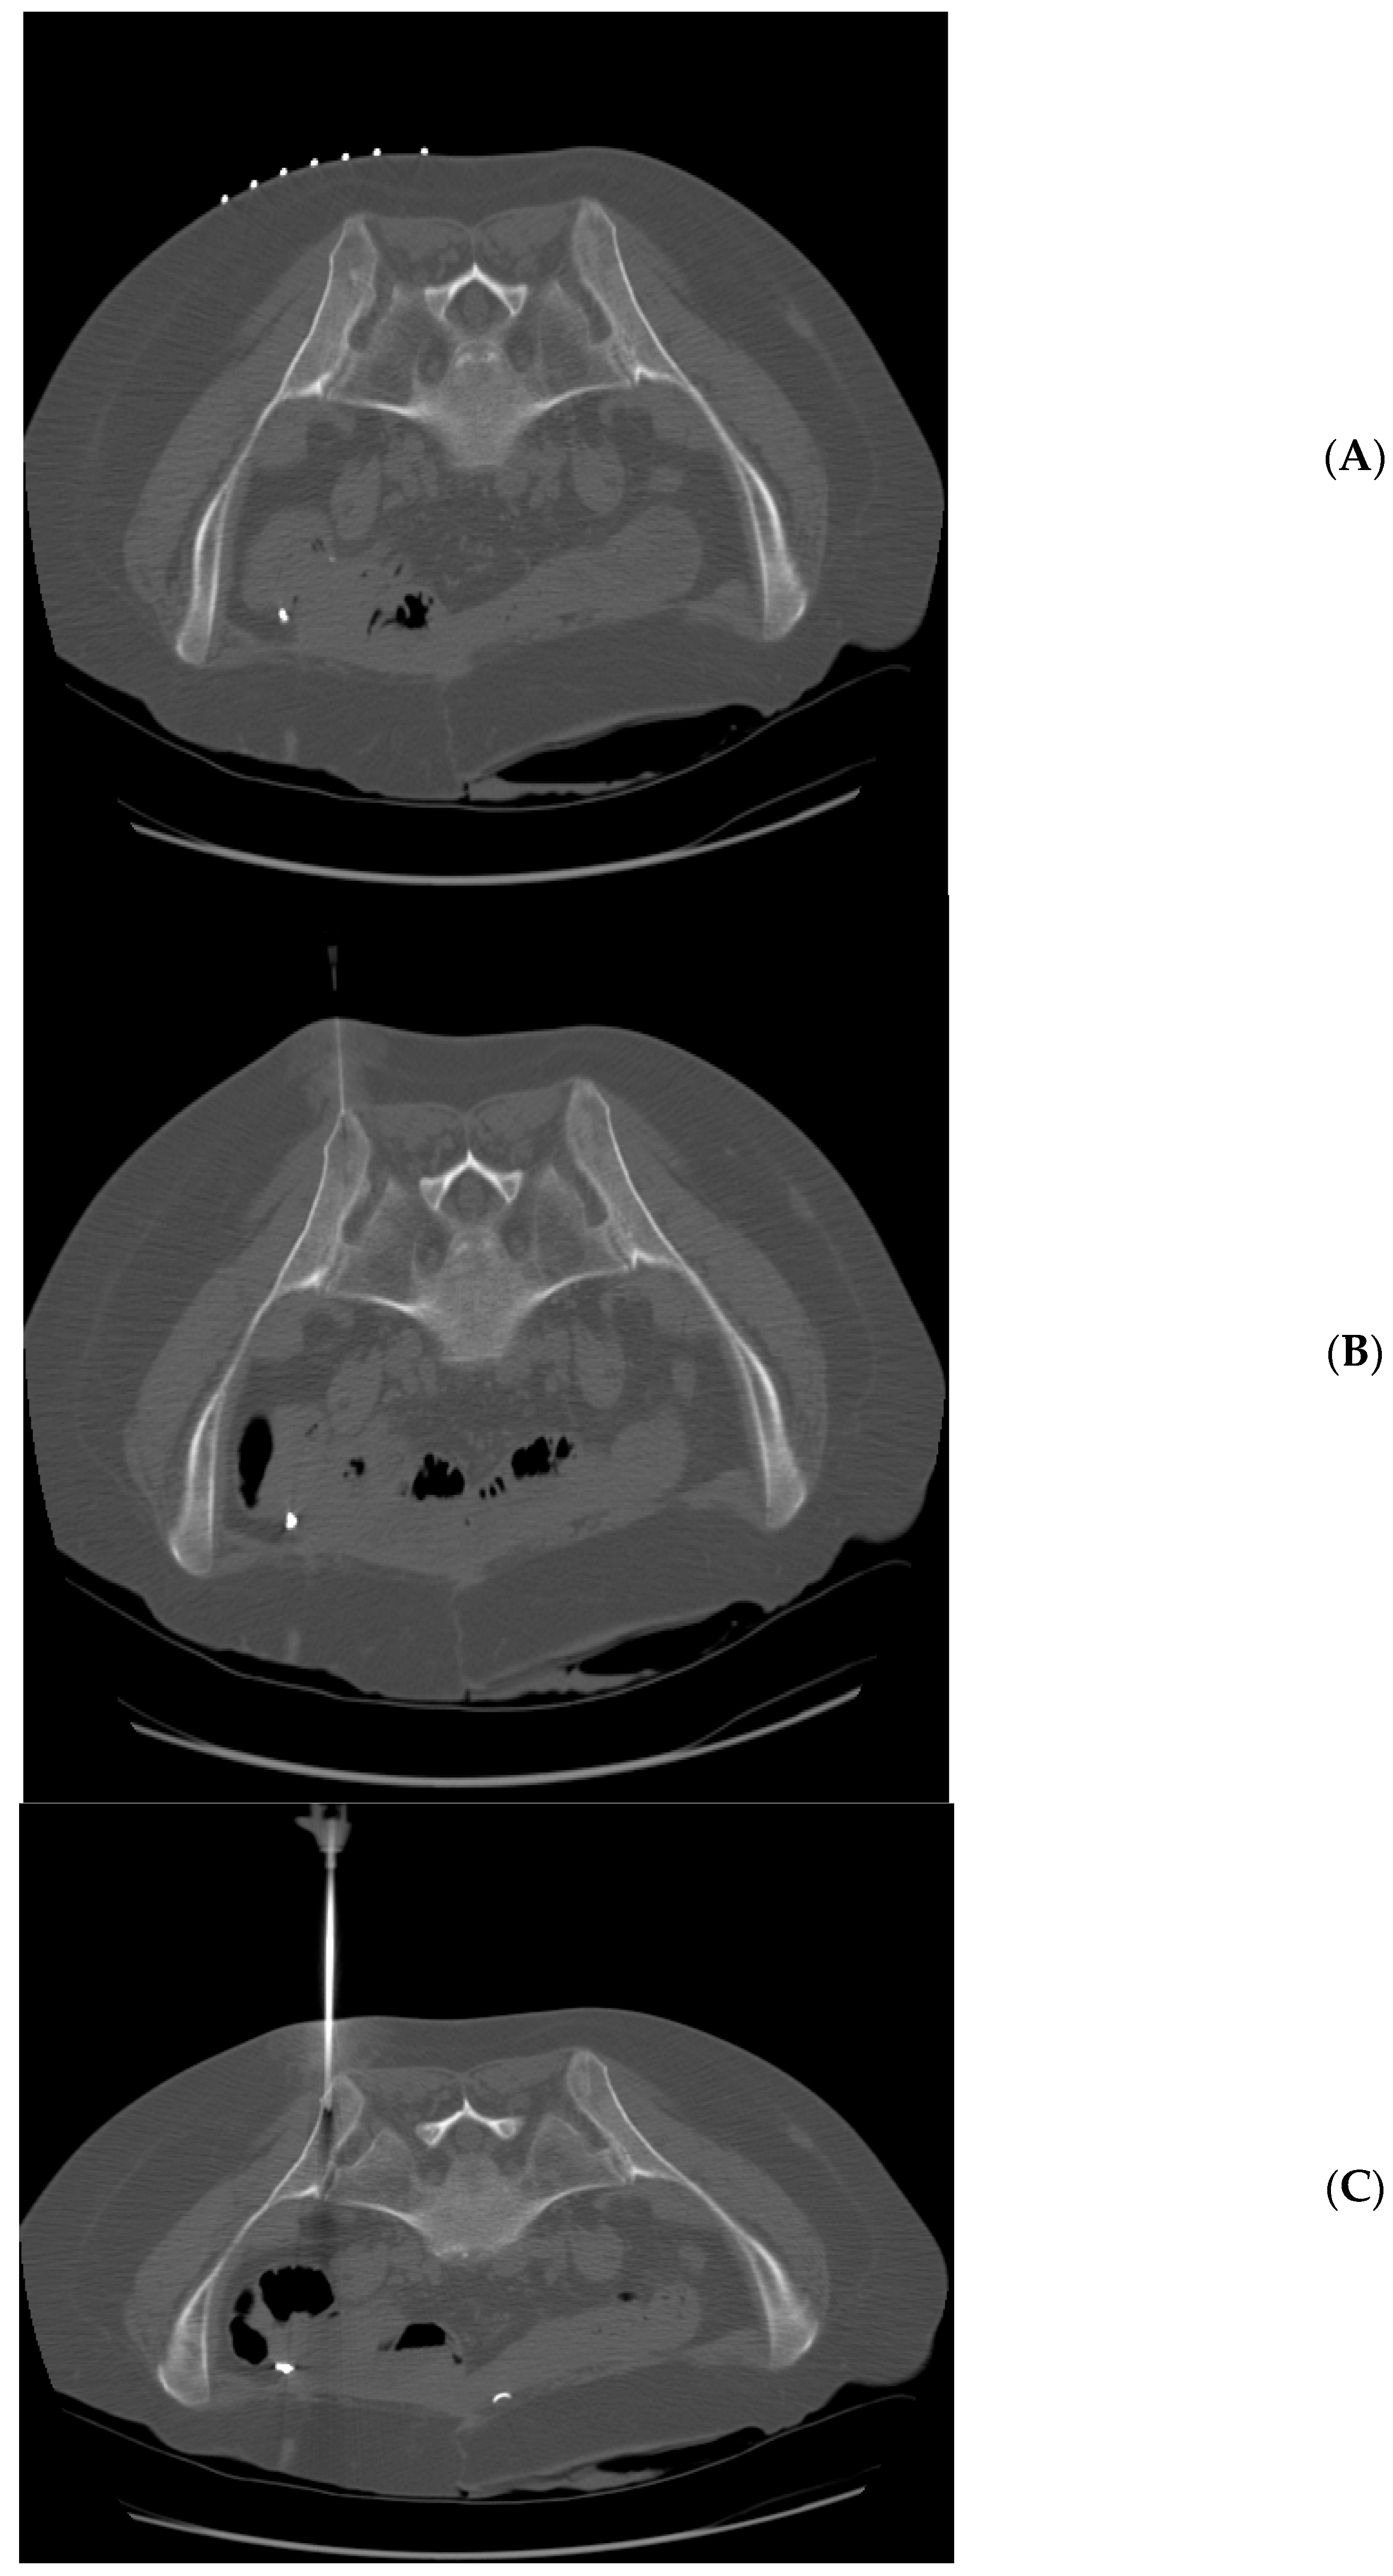

Figure 1.

71 year-old woman with acute myeloid leukemia. Technically successful biopsy, but insufficient pathologic diagnosis. (A) Prone position pre-planning CT with skin guidance markers on the right side of the patient. (B) Prone position CT with biopsy needle tip approaching right posterior iliac spine. (C) Prone position CT with biopsy needle tip within the right posterior iliac spine.